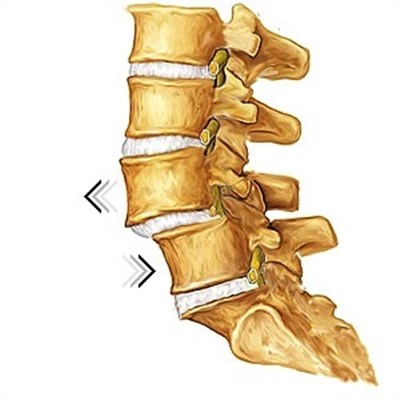

При смещении, один из позвонков сдвигается в сторону, нарушая нормальное функционирование позвоночника. В зависимости от того, в какую сторону сместился позвонок, выделяют три разновидности течения заболевания.

Самым распространенным считается антеспондилолистез, при котором позвонок сдвигается вперед. Сдвиг позвонка назад, получил название ретроспондилолистез, а в какую-либо сторону – латероспондилолистез.

В подавляющем большинстве случаев, смещаются 4 или 5 позвонок, что обусловлено повышенной нагрузкой на эту часть спины. Это очень опасное и болезненное состояние, требующее длительной комплексной терапии. Кроме того, при сдвиге пятого позвонка, обязательно диагностируют растяжение связок, подвывихи, что нередко требует проведения хирургической операции.